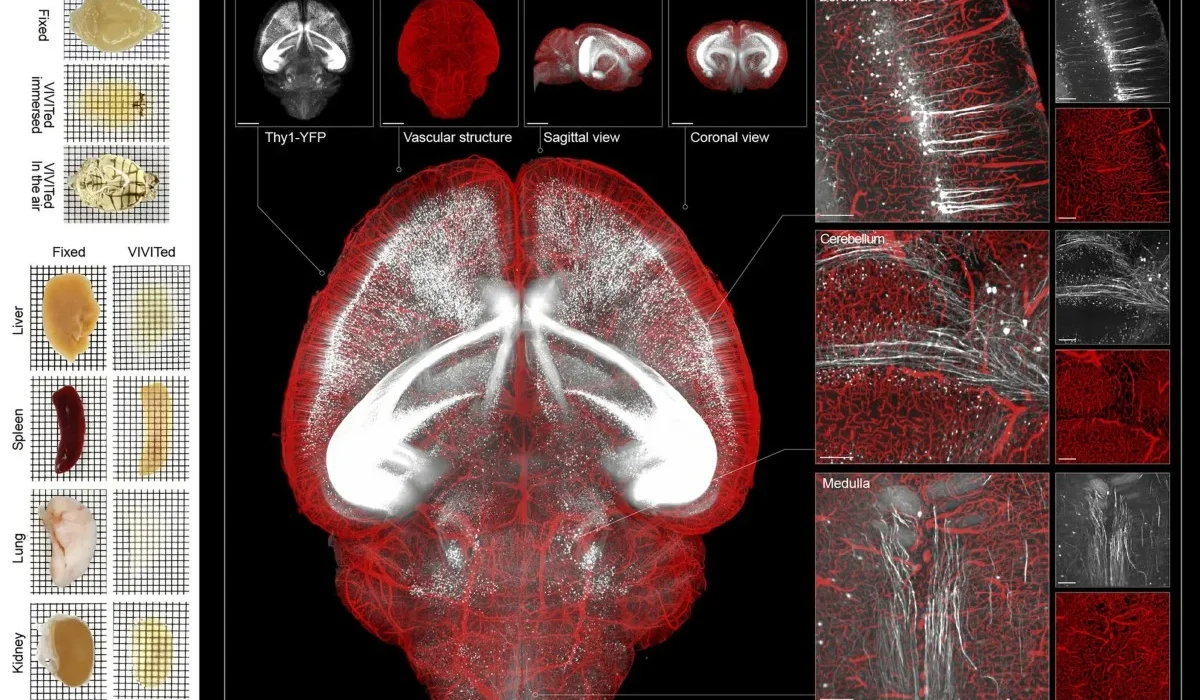

சீனாவில் அறுவை சிகிச்சை செய்யாமல், மூளையில் ஏற்படும் துல்லியமான மாற்றங்களைக் கண்டறிவதற்கு உதவும் அதிநவீன MRI இமேஜிங் ஸ்கேன் கண்டுபிடிக்கப்பட்டுள்ளது.

மூளை-கணினி இடைமுக (BCI) தொழில்நுட்பத்தில் பயன்படுத்தக்கூடிய வகையில் இந்த MRI ஸ்கேன் கண்டுபிடிக்கப்பட்டுள்ளது.

இந்த அதிநவீன MRI இமேஜிங் ஸ்கேன் கடுமையான நரம்பு நிலைகளைக் கண்காணிக்கவும் மற்றும் மன ஆரோக்கியத்தை மதிப்பிடவும் உதவும் எனக் கூறப்படுகிறது.

புதிய தொழில்நுட்பத்தின் மூலம் அல்சைமர், பார்கின்சன் மற்றும் பக்கவாதம் போன்ற நோய்களை ஆரம்ப நிலையிலேயே கண்டறிய முடியும் என்று ஆராய்ச்சியாளர்கள் தெரிவித்துள்ளனர்.